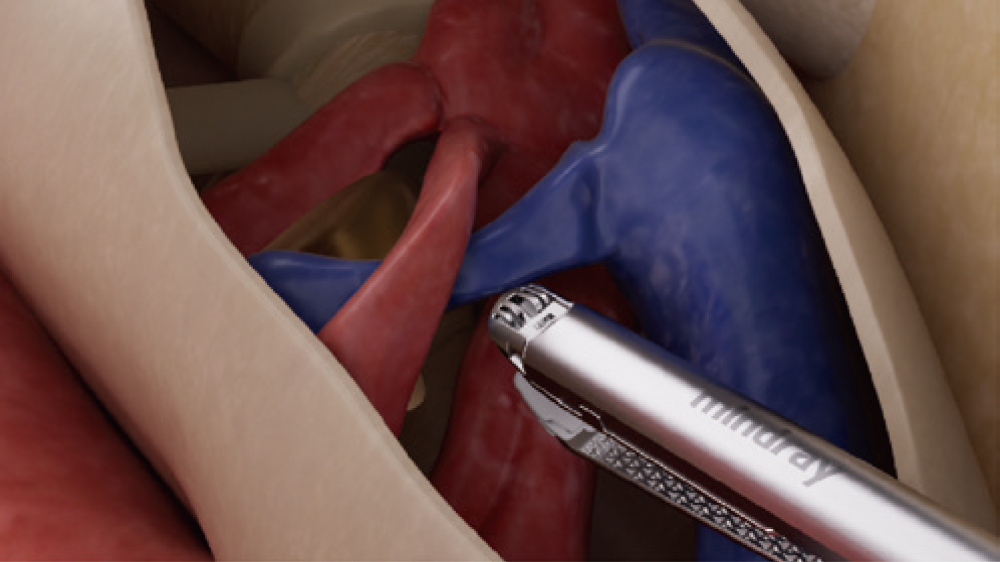

Mindray has developed an innovative endoscopic linear stapler that addresses clinical challenges caused by complex tissue conditions. By overcoming three key technical challenges - uniform tissue compression, precise stapling and smooth dissection, this device delivers safer anastomosis with reduced bleeding and leakage risks, ultimately achieving superior outcomes.

Detachable Curved Anvil Tip for Versatile Use

Single -step installation and removal designed for superior efficiency and convenience; Enables easy insertion through the hole in complex tubing structures, suitable for diverse applications, including cutting and stapling blood vessels and tissues.